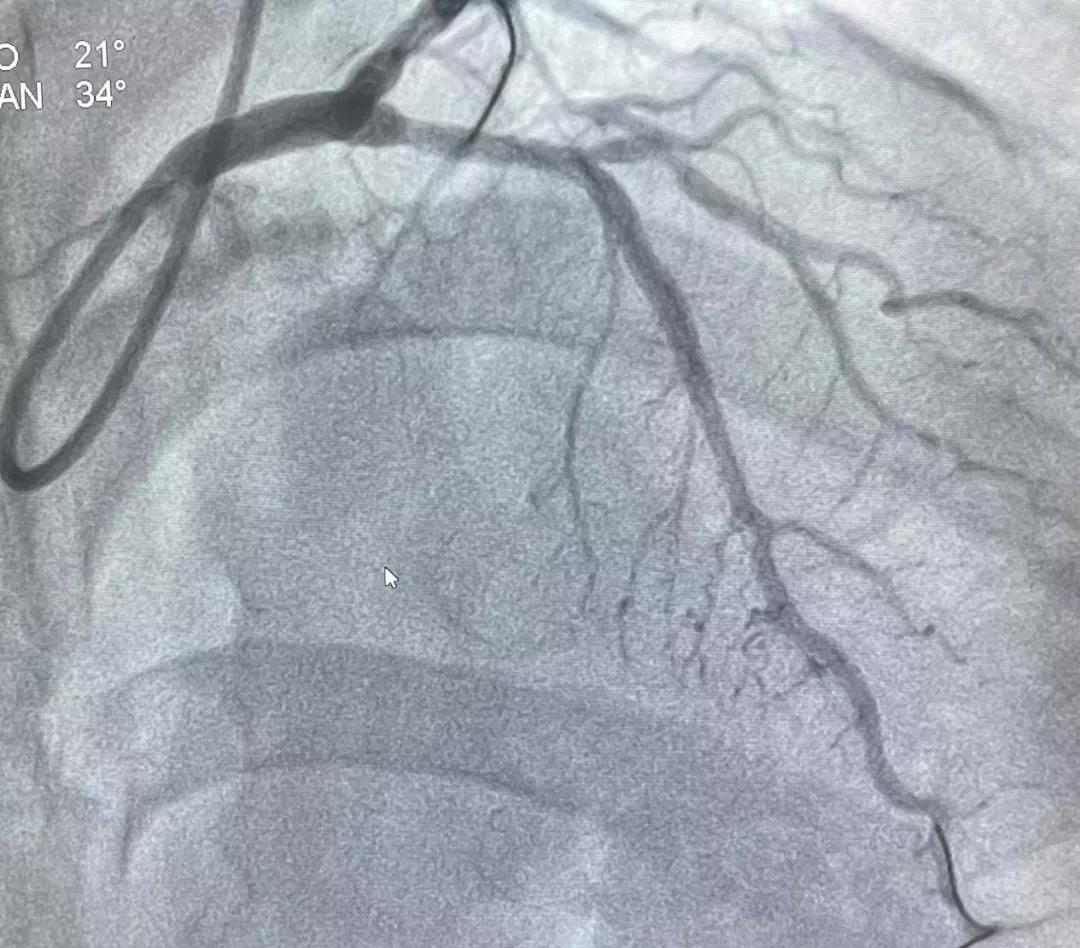

入院后,经过完善相关检查确诊小刘为心肌梗死,心血管内科团队立即为小刘行急诊冠状动脉造影,造影提示前降支近段99%狭窄,余冠脉未见明显狭窄。心血管内科毛艳阳主任考虑到患者为青年男性,为减轻患者心理负担,避免支架后的相关并发症,减少双抗药物应用时间,决定行药物球囊扩张术,必要时支架补救。经应用顺应性球囊、非顺应性球囊、切割球囊充分预处理后,行药物球囊扩张术,完成完全血运重建,手术顺利完成。患者小刘在没有植入支架的情况下实现了有效的介入治疗,践行了“介入无植入”的理念,目前已顺利出院,恢复良好。